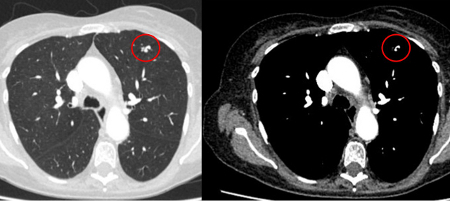

The remaining causes are infrequent and include mucoid impaction, septic emboli, arteriovenous malformations, and pulmonary amyloidosis.

[Figure caption and citation for the preceding image starts]: Computed tomography (CT) showing two areas (red circles) of mucoid impaction of the left upper lobe subsegmental bronchi, resulting in appearance that mimics a noduleFrom the collection of Dr George Tsaknis, MD, PhD, FRCP(London), MRQA, MAcadMEd, PGCert; used with permission [Citation ends].